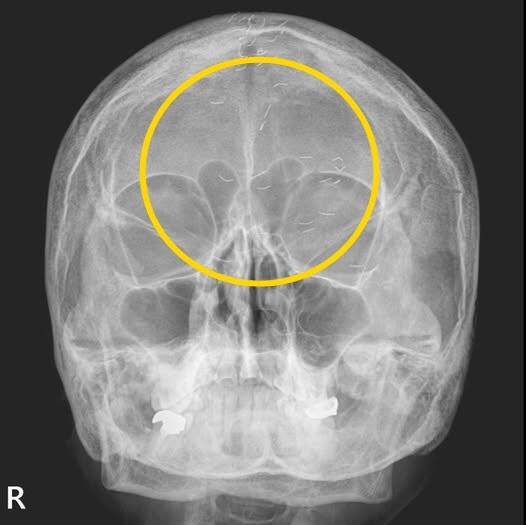

60대 여성 환자의 머릿속에 수많은 이물질이 흩어져 있는 모습이 담긴 엑스레이(X-ray) 사진이 주목을 받고 있다.

가정의학과 전문의 양성관씨는 최근 소셜네트워크서비스(SNS)에 한국형 진료라는 제목의 글을 올린 뒤 '금침요법의 흔적'이라고 설명했다.

양씨는 “엑스레이에서 1㎝ 크기의 다수 이물질이 발견됐다”며 “기생충인가? 전기칩인가? 외국이었다면 특이한 환자 사례로 ‘케이스 리포트’에 올랐을 사진”이라고 했다.

이어 “그러나 한국 의사들은 보자마자 헛웃음을 짓는다”고 했다. 이물질은 무릎·허리에서 자주 발견되지만 이번에는 머리에서 보였기 때문이다. 그는 “이물질의 정체는 기생충이나 전기칩이 아니라 ‘금침요법’의 흔적”이라고 했다.

금침요법은 얇은 순금을 1㎝ 미만의 길이로 등분한 뒤 통증 부위에 주입하는 치료법이다. 시술자들은 침이 몸속에서 해당 부위에 계속 자극을 줘 치료 효과를 높인다고 보고 있다. 환자는 머리 부분에 금침을 이용한 시술을 여러번 받은 것으로 추정된다.

이에 양씨는 ‘긴장성 두통’이라는 진단을 내렸다. 환자는 머리 중앙이 자주 아파 침 치료를 받고, 신경과에서도 자가공명영상(MRI)을 찍었지만 이상이 없었다고 했다.

양씨는 “MRI와 자기공명혈관영상(MRA) 검사결과 뇌출혈·뇌암·뇌경색 등의 이상 소견이 없었기에 긴장성 두통으로 확진했다”고 했다. 이미 정밀 검사를 받았으니 너무 걱정하지 말라고 전했다.